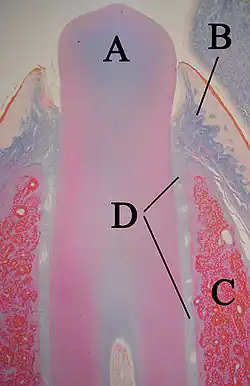

A: Zahnschmelz

B: Dentin

Einer der ersten Schritte bei der Bildung eines Zahns ist die Trennung von vestibulärer und dentaler Lamina. Die dentale Lamina verbindet die Zahnknospe für eine bestimmte Zeit mit der Epithelschicht im Mund.[2]

Feste Gewebe, darunter Zahnschmelz und Dentin, entwickeln sich in der nächsten Stufe, die als Kronenstadium (oder Reifestadium) bezeichnet wird. Zu dieser Zeit finden wichtige zelluläre Veränderungen statt. Die schnelle Teilung der Epithelzellen (Mitose), die in früheren Phasen zur Vergrößerung der Zahnknospe geführt hatte, endet nun an der Stelle, wo sich die Spitzen der Zähne bilden. Hier entstehen die ersten mineralisierten festen Gewebe. Gleichzeitig ändern die Zellen der inneren Epithel ihre Form von kubisch zu säulenförmig. Die Zellkerne bewegen sich von der Papille näher zum Stratum intermedium (Cate 1998:95[1]).

Die benachbarten Zellschichten der Papille wachsen plötzlich und differenzieren sich in Odontoblasten, die das Dentin bilden (Ross 2003:444[3]). Die Odontoblasten würden ohne die Veränderung im inneren Epithel nicht entstehen. Sie sondern ein Sekret, eine organische Matrix, in ihre unmittelbare Umgebung ab. Die Matrix enthält das für die Bildung des Dentins notwendige Material. Die Odontoblasten wandern dabei zum Zentrum der Papille. Im Gegensatz zum Zahnschmelz verläuft die Entstehung des Dentins also von außen nach innen. Auf dem Weg nach innen bleiben cytoplasmische Ausleger zurück. Die einzigartige, röhrenförmige Erscheinung des Dentins unter dem Mikroskop ist eine Folge seiner Bildung rund um diese Ausleger (Cate 1998:95[1]).

Die Zellen des inneren Epithels sondern eine organische Matrix gegen das Dentin ab, die sofort mineralisiert und zum Zahnschmelz wird. Außerhalb des Dentins befinden sich Ameloblasten, die die Bildung des Zahnschmelzes nach außen fortsetzen, so dass auf der Außenseite des entstehenden Zahns neues Material hinzugefügt wird.

Dentin

Die als Dentinogenese bezeichnete Bildung von Dentin ist das erste erkennbare Merkmal im Kronenstadium. Die verschiedenen Stufen führen zu unterschiedlichen Arten von Dentin: Manteldentin (Korff-Dentin) sowie primäres, sekundäres und tertiäres Dentin.

Die dentinbildenden Odontoblasten differenzieren sich von den Zellen der Zahnpapille. Sie beginnen, eine organische Matrix rund um die zukünftige Spitze des Zahns nahe dem inneren Epithel abzusondern. Diese Matrix enthält Collagen-Fasern mit einem großen Durchmesser von 0,1–0,2 μm. (Cate 1998:136)[1] Die Odontoblasten bewegen sich zum Zentrum des Zahns und bilden einen Ableger, den man als Odontoblasten-Prozess bezeichnet. (Cate 1998:95)[1] Dieser führt zur Sekretierung von Hydroxyapatit-Kristallen und zur Mineralisation der Matrix. Die etwa 150 μm dicke Schicht ist das Manteldentin. (Cate 1998:138)[1]

Während das Manteldentin aus einer bereits existierenden Grundsubstanz der Zahnpapille entsteht, entwickelt sich das primäre Dentin auf andere Weise. Die Odontoblasten werden so groß, dass keine extrazellulären Ressourcen zu einer organischen Matrix beitragen können. Die größeren Odontoblasten sondern das Kollagen in kleineren Mengen ab, wodurch klarer strukturierte, heterogene Kerne entstehen. Darüber hinaus werden weitere Substanzen wie Lipide, Phosphoproteine und Phospholipide abgesondert. (Cate 1998:139)[1]

A: Dentin

B: Wurzelzement